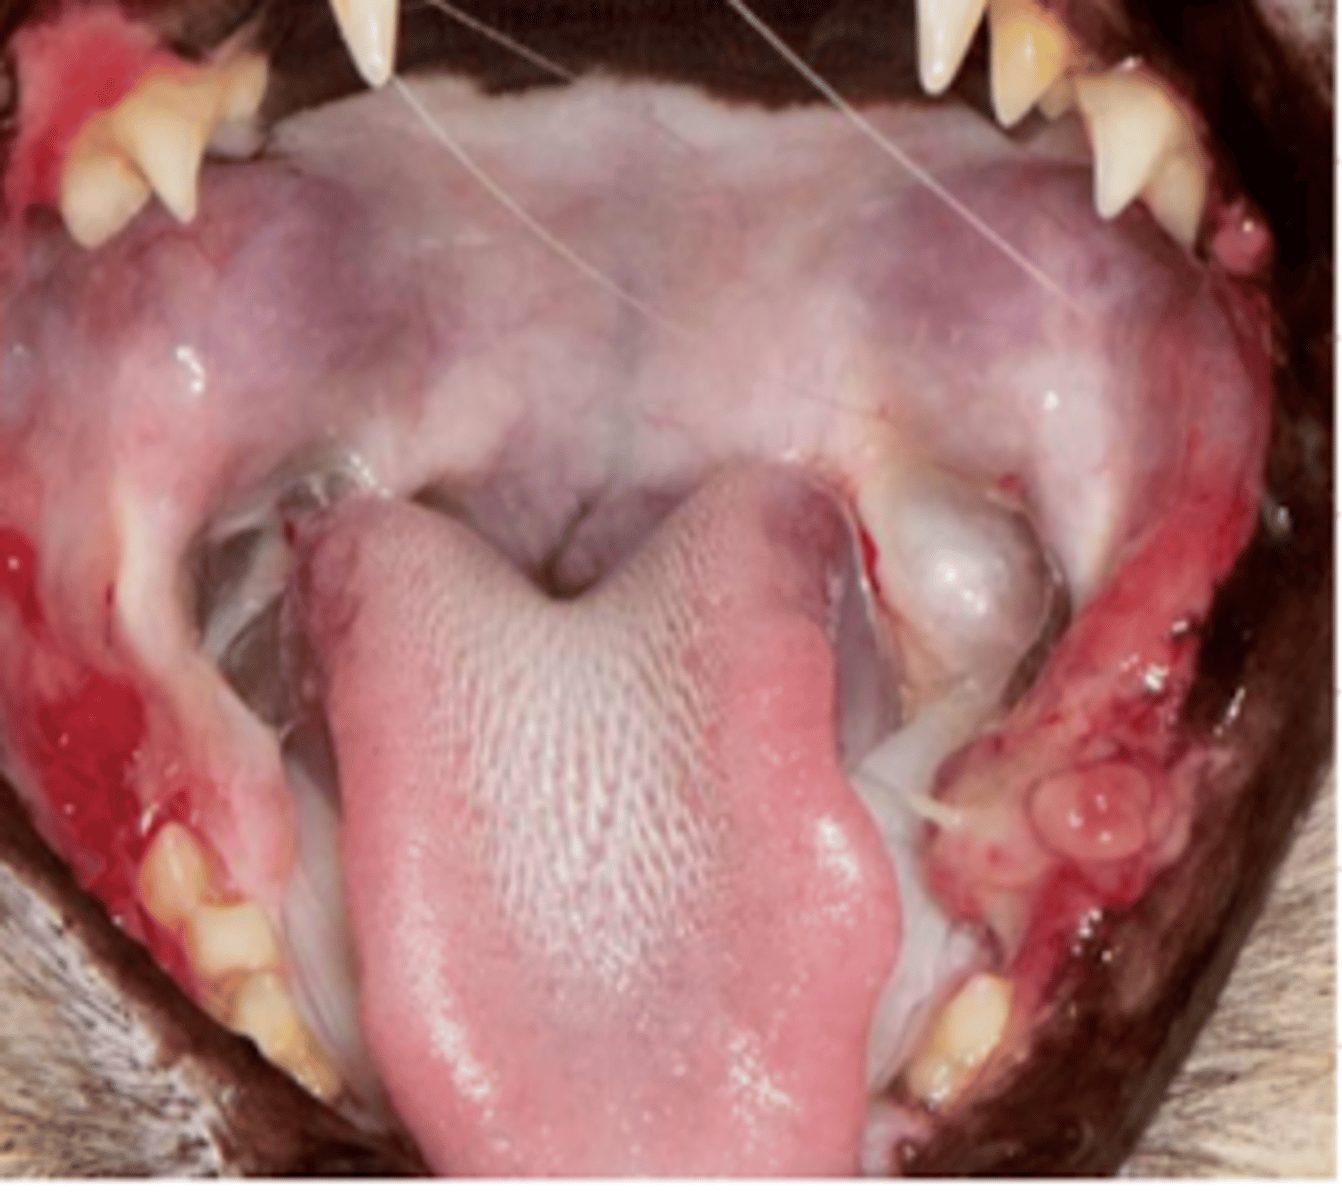

gingivitis; viral infection

what is the medical term for the condition of this cat? what is likely the etiology?

stomatitis

what does this cat have?

stomatitis

this cat has what condition?